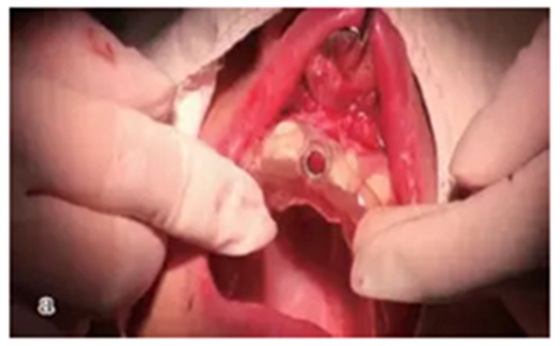

翻瓣種植

設(shè)計(jì)切口,剝離黏骨膜后,將截骨導(dǎo)板戴到骨面上,用咬骨鉗沿著截骨導(dǎo)板平面進(jìn)行截骨,并用骨銼修整骨平面,截骨完成后將種植導(dǎo)板固定在骨面上進(jìn)行種植備孔,完成后植入種植體。注意截骨平面要平整,否則影響種植導(dǎo)板的就位。

圖17 截骨與備孔:a.戴上截骨導(dǎo)板后進(jìn)行截骨并修平骨面;b. 戴上種植導(dǎo)板進(jìn)行備孔